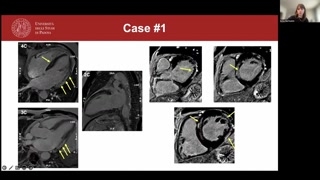

So to show you somecases, this is a fifty-five-year-old malewith hypertension, dyslipidemia, obesity.He had no family historyof heart disease, and he presentedbecause of palpitations.He was prescribed an exercisetesting, and he had ventricular arrhythmiason effort.An echo was m-barely normal,only showing a mildly dilated leftventricle with, with preserved function,and therefore we performed, um, CMR.Coronaries were, of course, uh,normal on angiogram.

So as you see here,we have, uh, a mildly dilatedleft ventricle with a borderlinelow normal ejection fraction because ofsome regional wall motion abnormalitieshere in the anterolateral mid wall.

And when we look atparametric mapping, what we see isthat we have a mildincrease in T2 values compared towhat is normal in ourlab, and it's mainly abnormal herein the, um, posterior wall.Uh, we also have increasednative T1 values.As you see here, wehave eleven hundred as compared tothe one thousand and forty,which is the upper range ofnormal in our lab.And we also have anincrease in the extracellular volume, whichis above the th-thirty percentthat is the upper range ofnormal in our lab.

If we perform late enhancementsequences, normal myocardium appears black, andlate enhancement is a brightsignal.Uh, you see that wehave quite a lot of lateenhancement, mainly in the basallateral wall, as confirmed both onthe long-axis and the short-axissequences, but we also have somemid-wall, uh, involvement of thebasal septum.So here we have anon-ischemic late enhancement, uh, because yousee here the subendocardium isspared, and it's a mid-wall distribution.

Uh, so we can concludethe patient has, uh, myocardial inflammation,acute myocardial inflammation because wehave the T2 criterion, as shownby the T2 mapping, andthe T1 criterion of m- non-ischemicmyocardial injury, as shown bythe, by the non-ischemic, um, LGof the left ventricle andthe increased native T1 and ECV,uh, values.